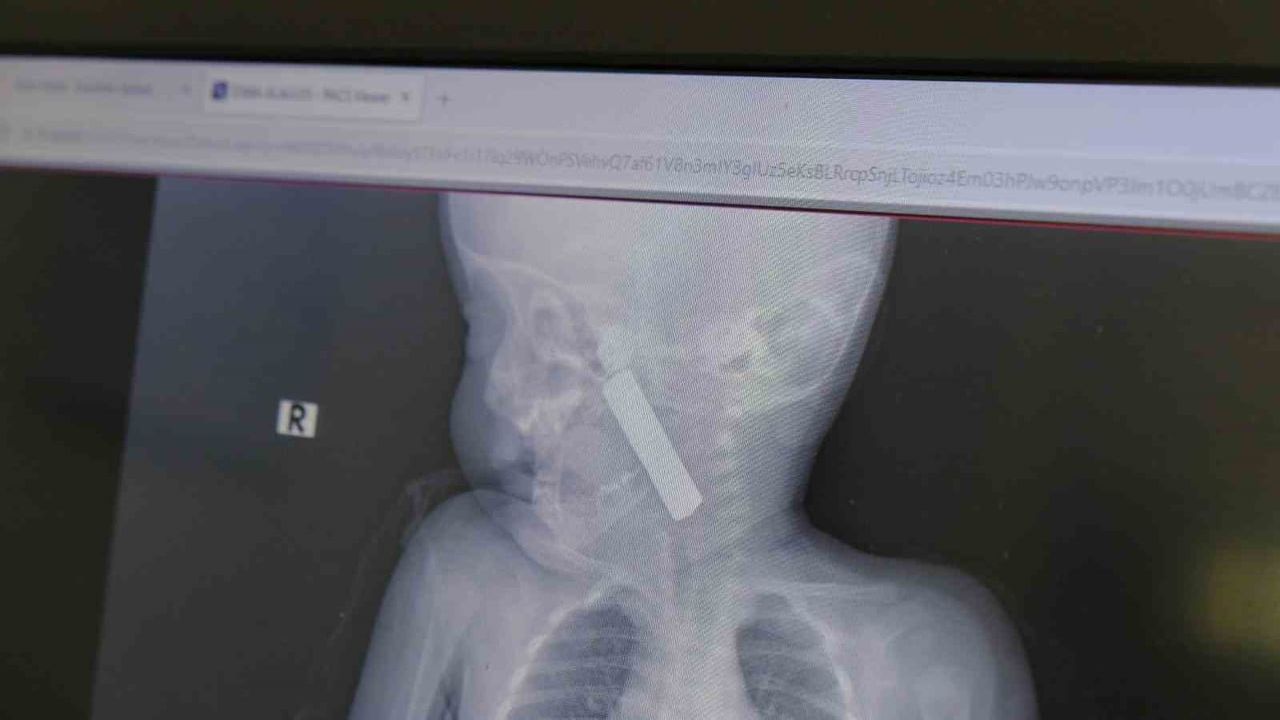

Karaman Eğitim ve Araştırma Hastanesi acil servisine kusma şikayetiyle getirilen 6 aylık E.A. isimli kız bebeğin yapılan muayene ve tetkiklerinde boğazına kumanda pili kaçtığı tespit edildi. Solunum güçlüğü yaşayan bebek, çocuk cerrahisi ekibi tarafından acilen ameliyata alındı.

Yapılan tetkiklerde pilin ağız tabanına oturduğu ve yemek borusunun birinci darlığına kadar uzandığı görüldü. İlk muayenede bebekte belirgin siyanoz ve solunum sıkıntısı vardı; oksijen satürasyonunun yaklaşık 90 civarında olduğu bildirildi. Durum acil olduğundan, ekip vakit kaybetmeden ameliyathaneye yöneldi.